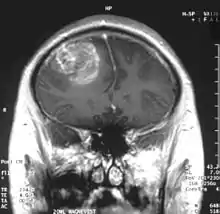

| Coronal MRI with contrast of a glioblastoma in a 15-year-old male | |

When viewed with MRI, glioblastomas often appear as ring-enhancing lesions. The appearance is not specific, however, as other lesions such as abscess, metastasis, tumefactive multiple sclerosis, and other entities may have a similar appearance.[58] Definitive diagnosis of a suspected GBM on CT or MRI requires a stereotactic biopsy or a craniotomy with tumor resection and pathologic confirmation. Because the tumor grade is based upon the most malignant portion of the tumor, biopsy or subtotal tumor resection can result in undergrading of the lesion. Imaging of tumor blood flow using perfusion MRI and measuring tumor metabolite concentration with MR spectroscopy may add diagnostic value to standard MRI in select cases by showing increased relative cerebral blood volume and increased choline peak, respectively, but pathology remains the gold standard for diagnosis and molecular characterization.